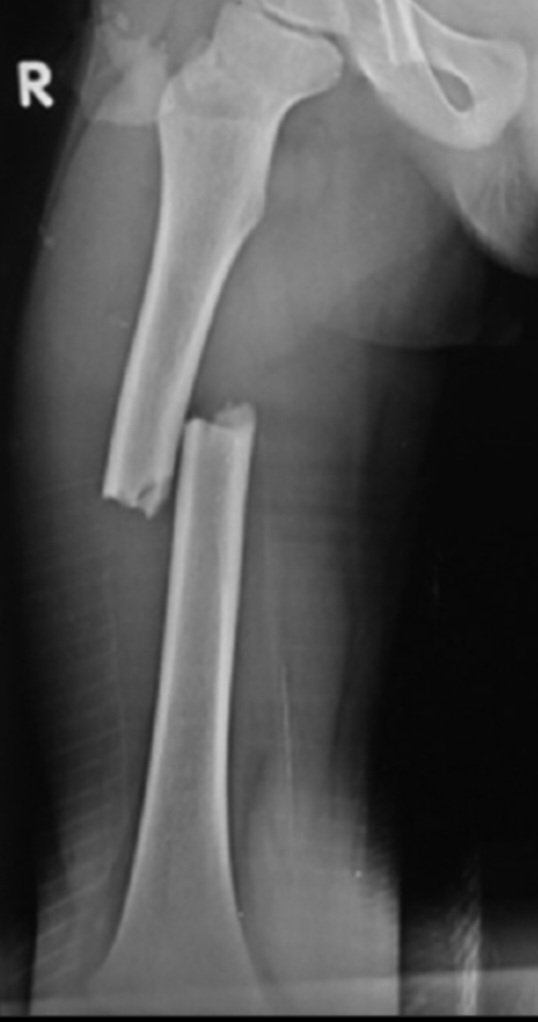

1- الأشعة السينية X-Ray:

- تستخدم للفحوصات الروتينية.

- سريعة وغير مكلفه ماديا.

- الأكثر شيوعًا ومتاح على نطاق واسع.

- تأخذ صورة ثنائية الأبعاد(2D).

- تستخدم في الإصابات لكشف الكسور.

- تستخدم ايضا لكشف الالتهاب الرئوي في الصدر وبعض الاورام السرطانية.

- نسبة الإشعاع بسيطة.